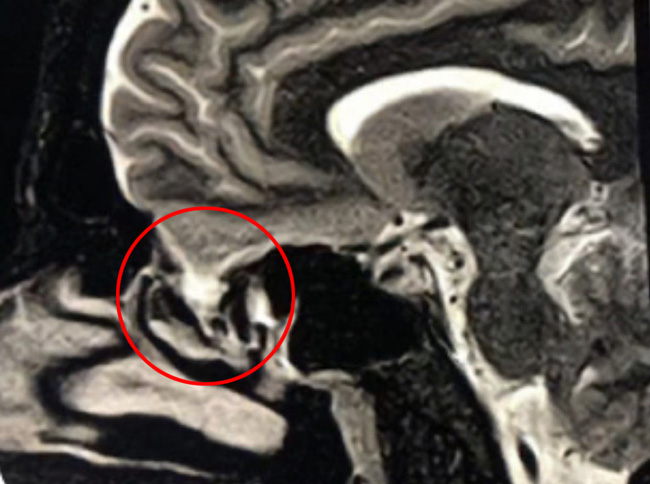

This is a 39 year old physician with a long history of sinus issues, who more recently had noted an increased drainage of clear fluid from his nose. Testing of the fluid for Beta-2-transferrin demonstrated that it was consistent with cerebrospinal fluid (csf). MRI and CT scan demonstrated an encephalocele in the frontal most part of the anterior skull base, on the left, just off midline (Figures 1a,1b,1c). For the last 3 weeks, he has also been having headaches and neck pain.

Figure 1b – Sagittal CT bone window